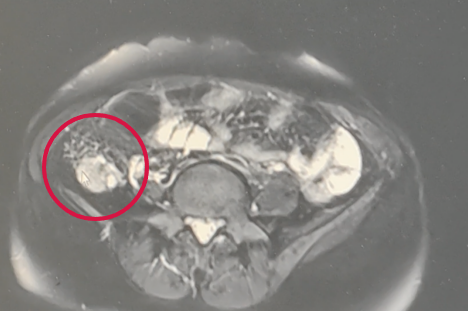

阿赛术前2程新辅助化疗后

下一步,手术。由于阿赛病灶广泛,肿瘤邻近肠管、膀胱、输尿管等重要脏器损伤,手术难度大。无影灯下,医疗团队在手术台上默契地配合,超声刀每一步都如单脚走钢丝般小心前进。最终凭借精湛的手术技巧,团队于2023年6月,顺利将腹腔各器官表面的肉眼可见的肿瘤病灶均做了切除,完成了肿瘤细胞减灭术、盆腔粘连松解术和盆腔淋巴结清扫术,达到R0标准。术后病理符合(右卵巢)低分化浆液性腺癌,大网膜转移。